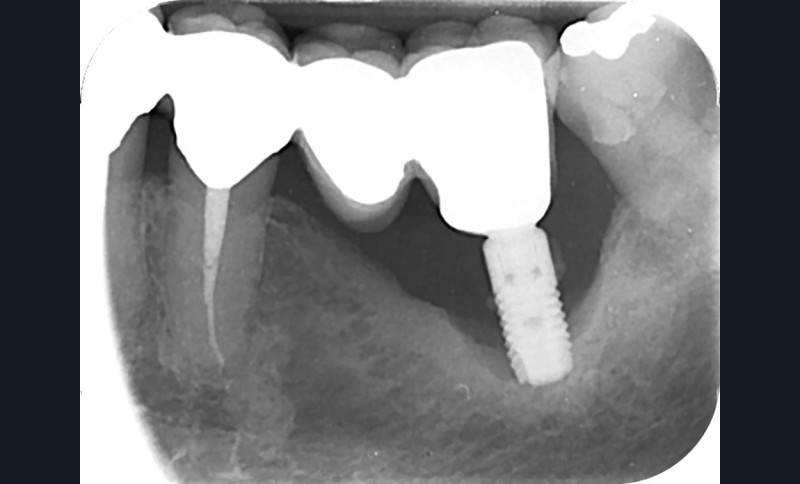

Le mode d’assemblage (prothèse vissée ou scellée) retenu peut aussi influencer la survenue d’une péri-implantite, avec une corrélation importante entre survenue de péri-implantite et présence d’excès de ciment de scellement [13, 14]. Une connexion dent-implant (prothèse dento-implanto-portée) est à proscrire, car plus propice aux péri-implantites et échecs mécaniques (fig. 4 et 5) [15, 16].